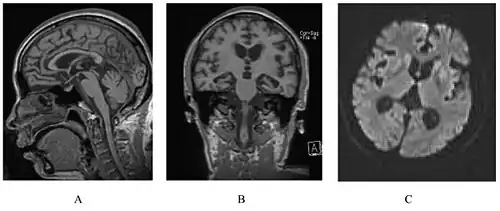

A person with inherited prion disease has cerebellar atrophy. This is typical for GSS.